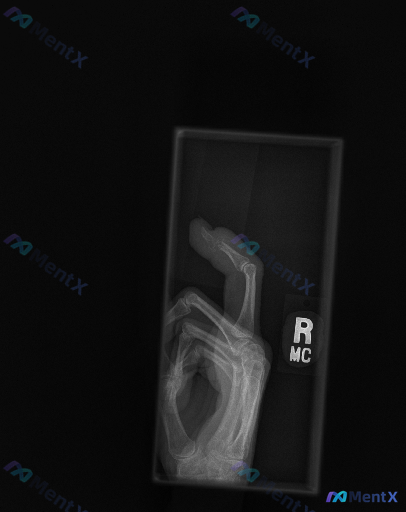

整理了一张右侧手部侧位X光片的影像资料,先把客观的影像表现放出来,大家第一眼会怎么判断? 客观影像表现(已整理) 1. 骨骼与关节:右侧第一掌骨基底部可见明显皮质中断、骨折线,有骨块分离,关节面紊乱;第一腕掌关节(CMC关节)对位严重失常,掌骨基底部向背侧/桡侧移位,关节间隙消失。 2. 其他关节:...